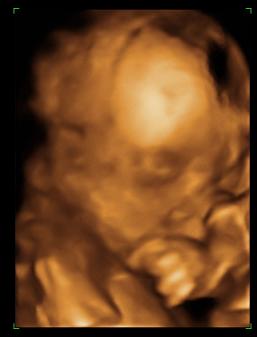

Ma voltam uh-n. Minden ok!!! :D Ficánka gyönyörűen fejlődik, mindene pont akkora, mint kell, és még mindig fiú! :D :D

550 gr már! :D

Majd teszek fel pocak meg baba képeket is, csak le kell kicsinyítenem.

Nagyon szép a kicsi fiú! :):):)

De csodás!!!!!!! Azokkal a lábikókkal aztán jól oda tud küldeni anyucinak????!!!!! :wink: Édes ez a pici Dávid már most! :D :P :D

Honey: Szépen megmutatta magát a fiatalember, hogy szopizza a kis kezét, nagyon aranyos :)